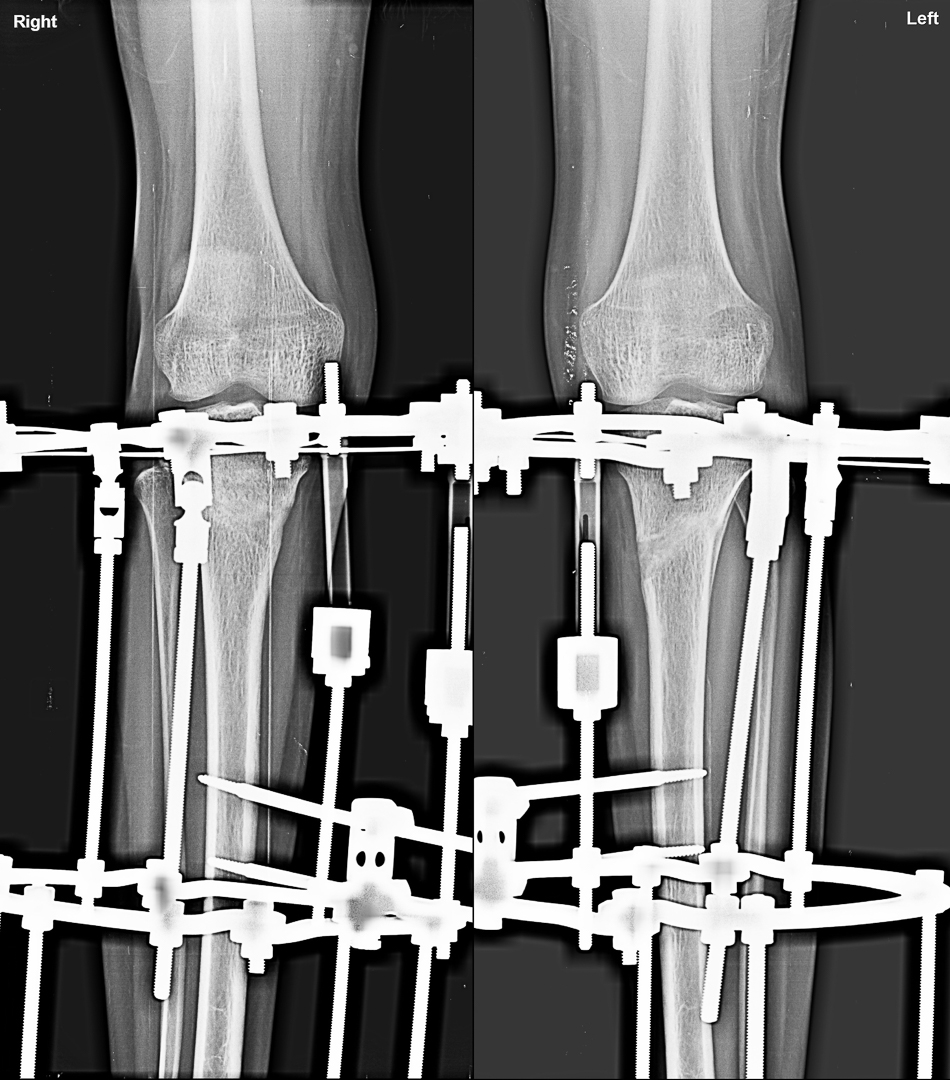

Expert orthopedic deformity correction at Trishla Ortho — tailored treatments for congenital and acquired bone misalignments in children and adults using modern procedures like osteotomy, external fixation, and more.